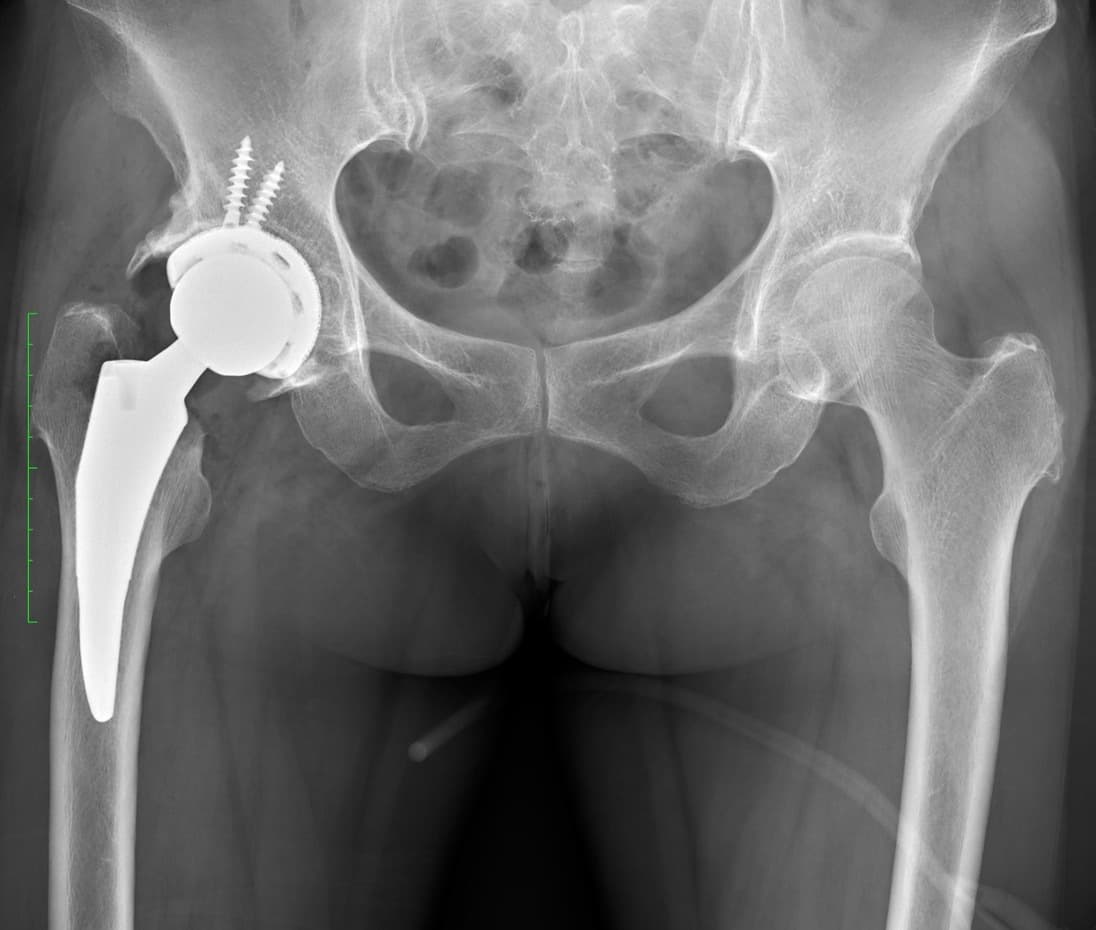

手術の1年半前より右股関節痛が出現し、徐々に歩行時痛は増強し夜間も右股関節〜大腿部へ疼くような疼痛も出現、術前は疼痛による右下肢への荷重困難と股関節の可動域制限、筋力低下により屋内では壁伝いで7m程度、屋外では足を引きずる形で10分程度の歩行耐久性でした(動画)。また足が開きにくいことで靴下の着脱や足の爪切り動作の困難感がみられました。近医での治療行うも症状改善なく当院へ2023年3月受診され、右変形性股関節症の診断あり同年5月に右人工股関節置換術が行われました。

術後4日目には1本杖使用しトイレ移動や洗面までの自立歩行が可能となりました。術後1週目には靴下着脱や靴の着脱が可能となり(動画)、術後2週目には補助具なしで自立歩行が可能となり(動画)、足の爪切り動作も自立して行えるようになっています(動画)。術後3週目には20分の屋外歩行を行い安定性・スピード共に実用的に問題なく可能(動画)となりました。また、浴槽へのまたぎ動作や階段昇降も自立し、術後26日目に自宅退院の運びとなっています。